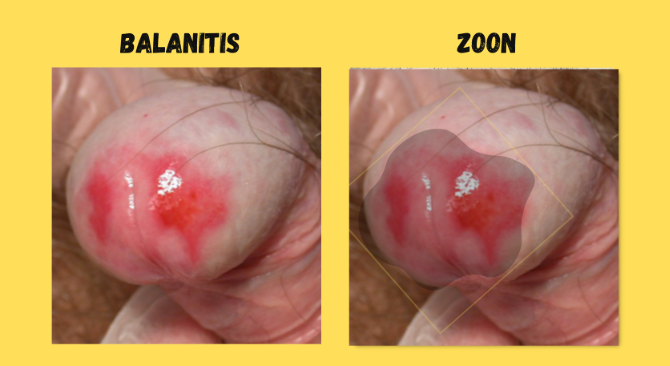

BALANITIS La balanitis es la inflamación del glande del pene, y cuando también compromete el prepucio se denomina balanopostitis. CAUSAS MÁS FRECUENTES Infecciosas Hongos(principalmente Candidiasis – Candida albicans) → la más común Bacterias (estreptococos,...